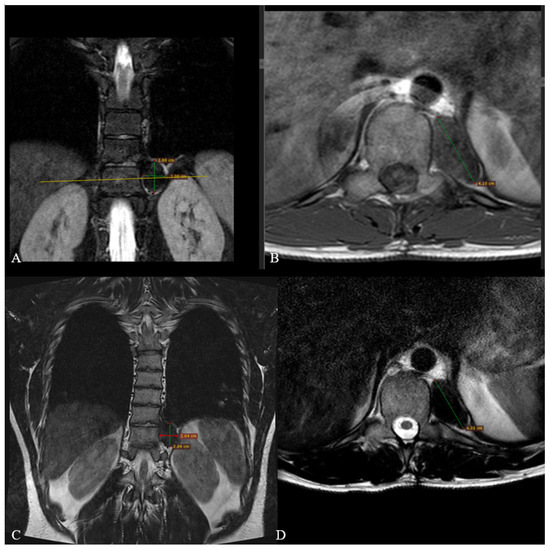

2. Case Report